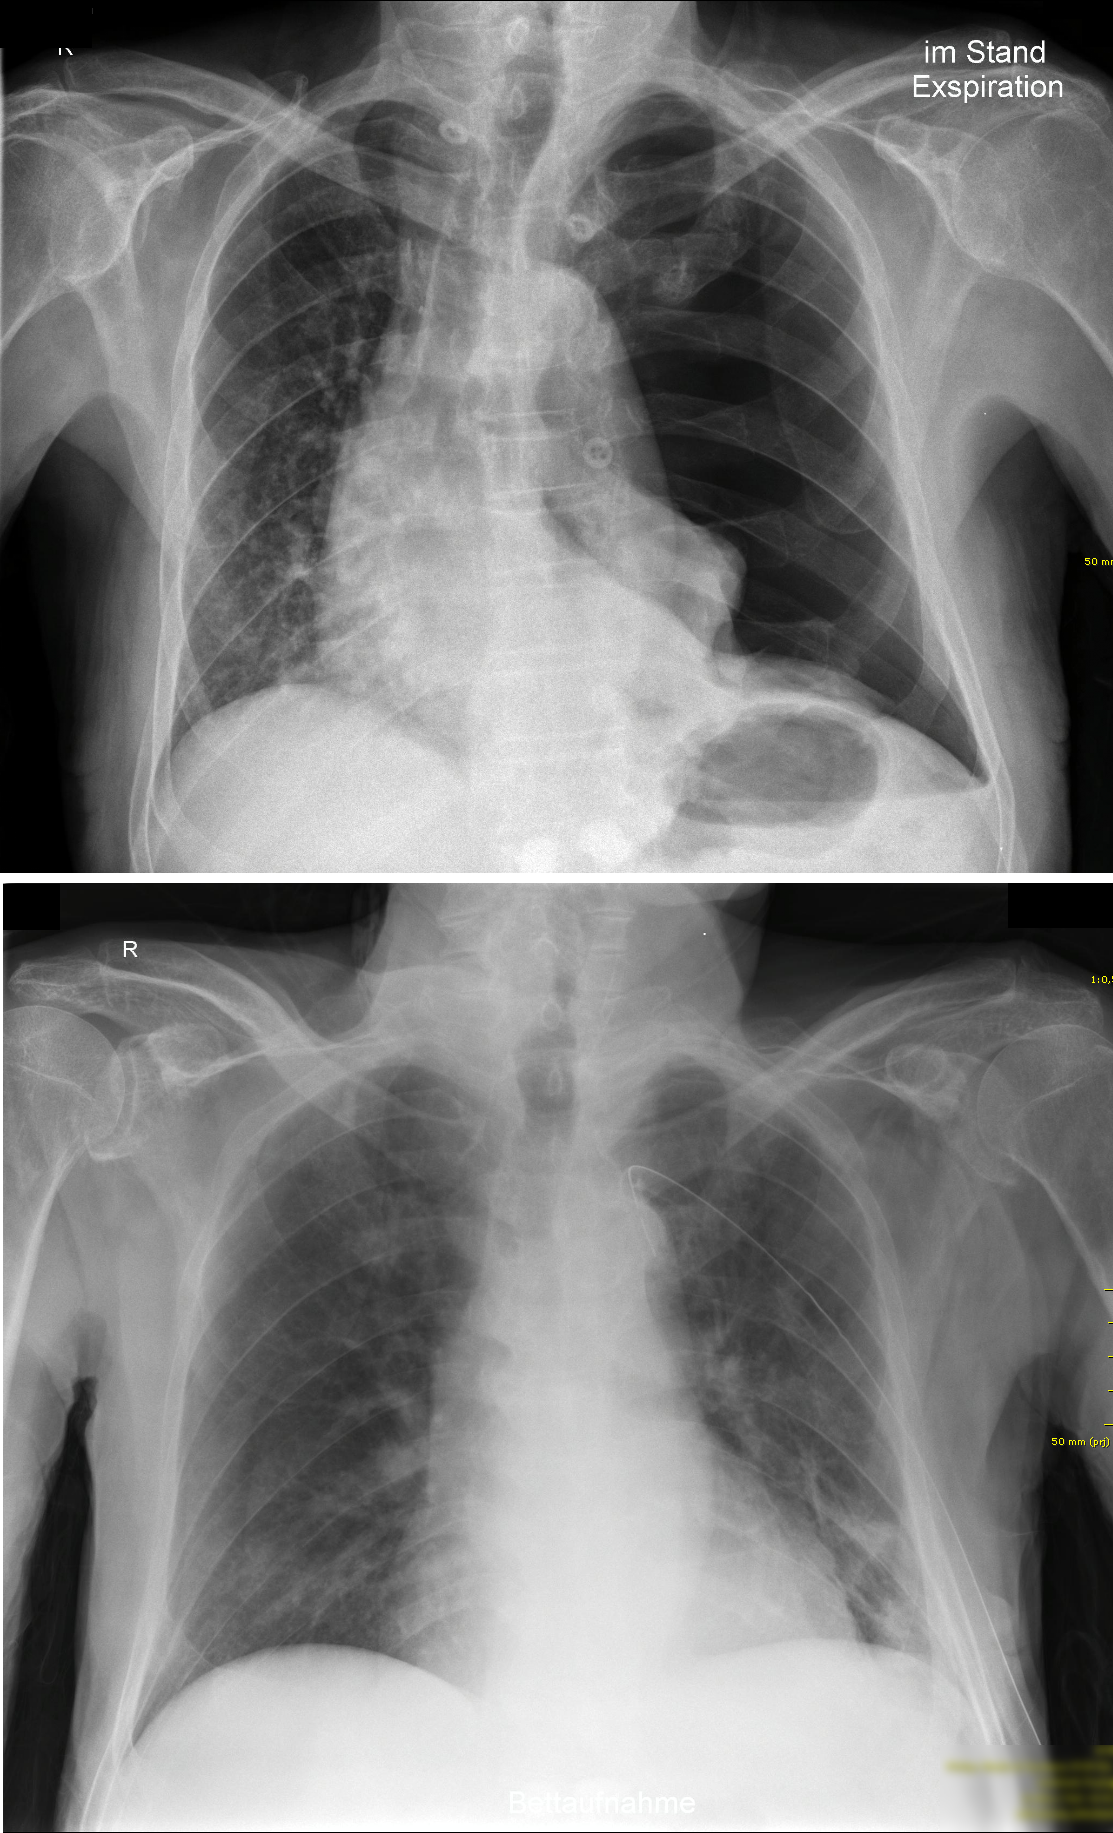

Bildgebung

Ein linksseitiger Spannungspneumothorax vor (oben) und nach (unten) Anlage einer Thoraxdrainage. Gut zu sehen ist die Verlagerung des Mediastinums hin zur gesunden Seite. © wikipedia.org/Cupr78up, CC BY-SA 3.0

Am besten lässt sich ein Pneumothorax im Röntgenthorax (in Expiration und Inspiration) oder im CT darstellen.